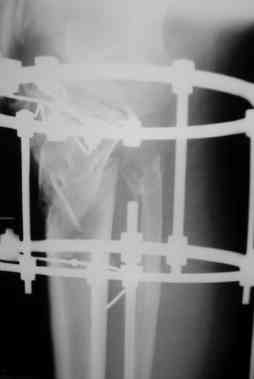

Р-граммы за март и апрель

> Р-граммы за март и апрель

Постараться отрепонировать наружное плато, вероятно с костной пластикой. Фиксация метафизарного перелома пластиной LCP PLT (дорого и локальный статус ноги должен быть соответствующий), если нет - то по Илизарову (заметьте - не спицами и кольцами от аппарата И., а по методу И.).